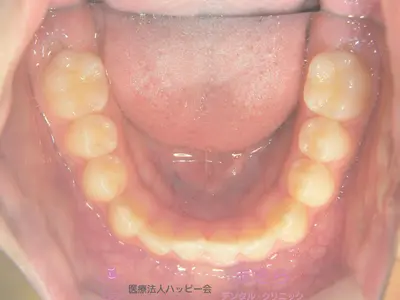

初診時

case-001-3